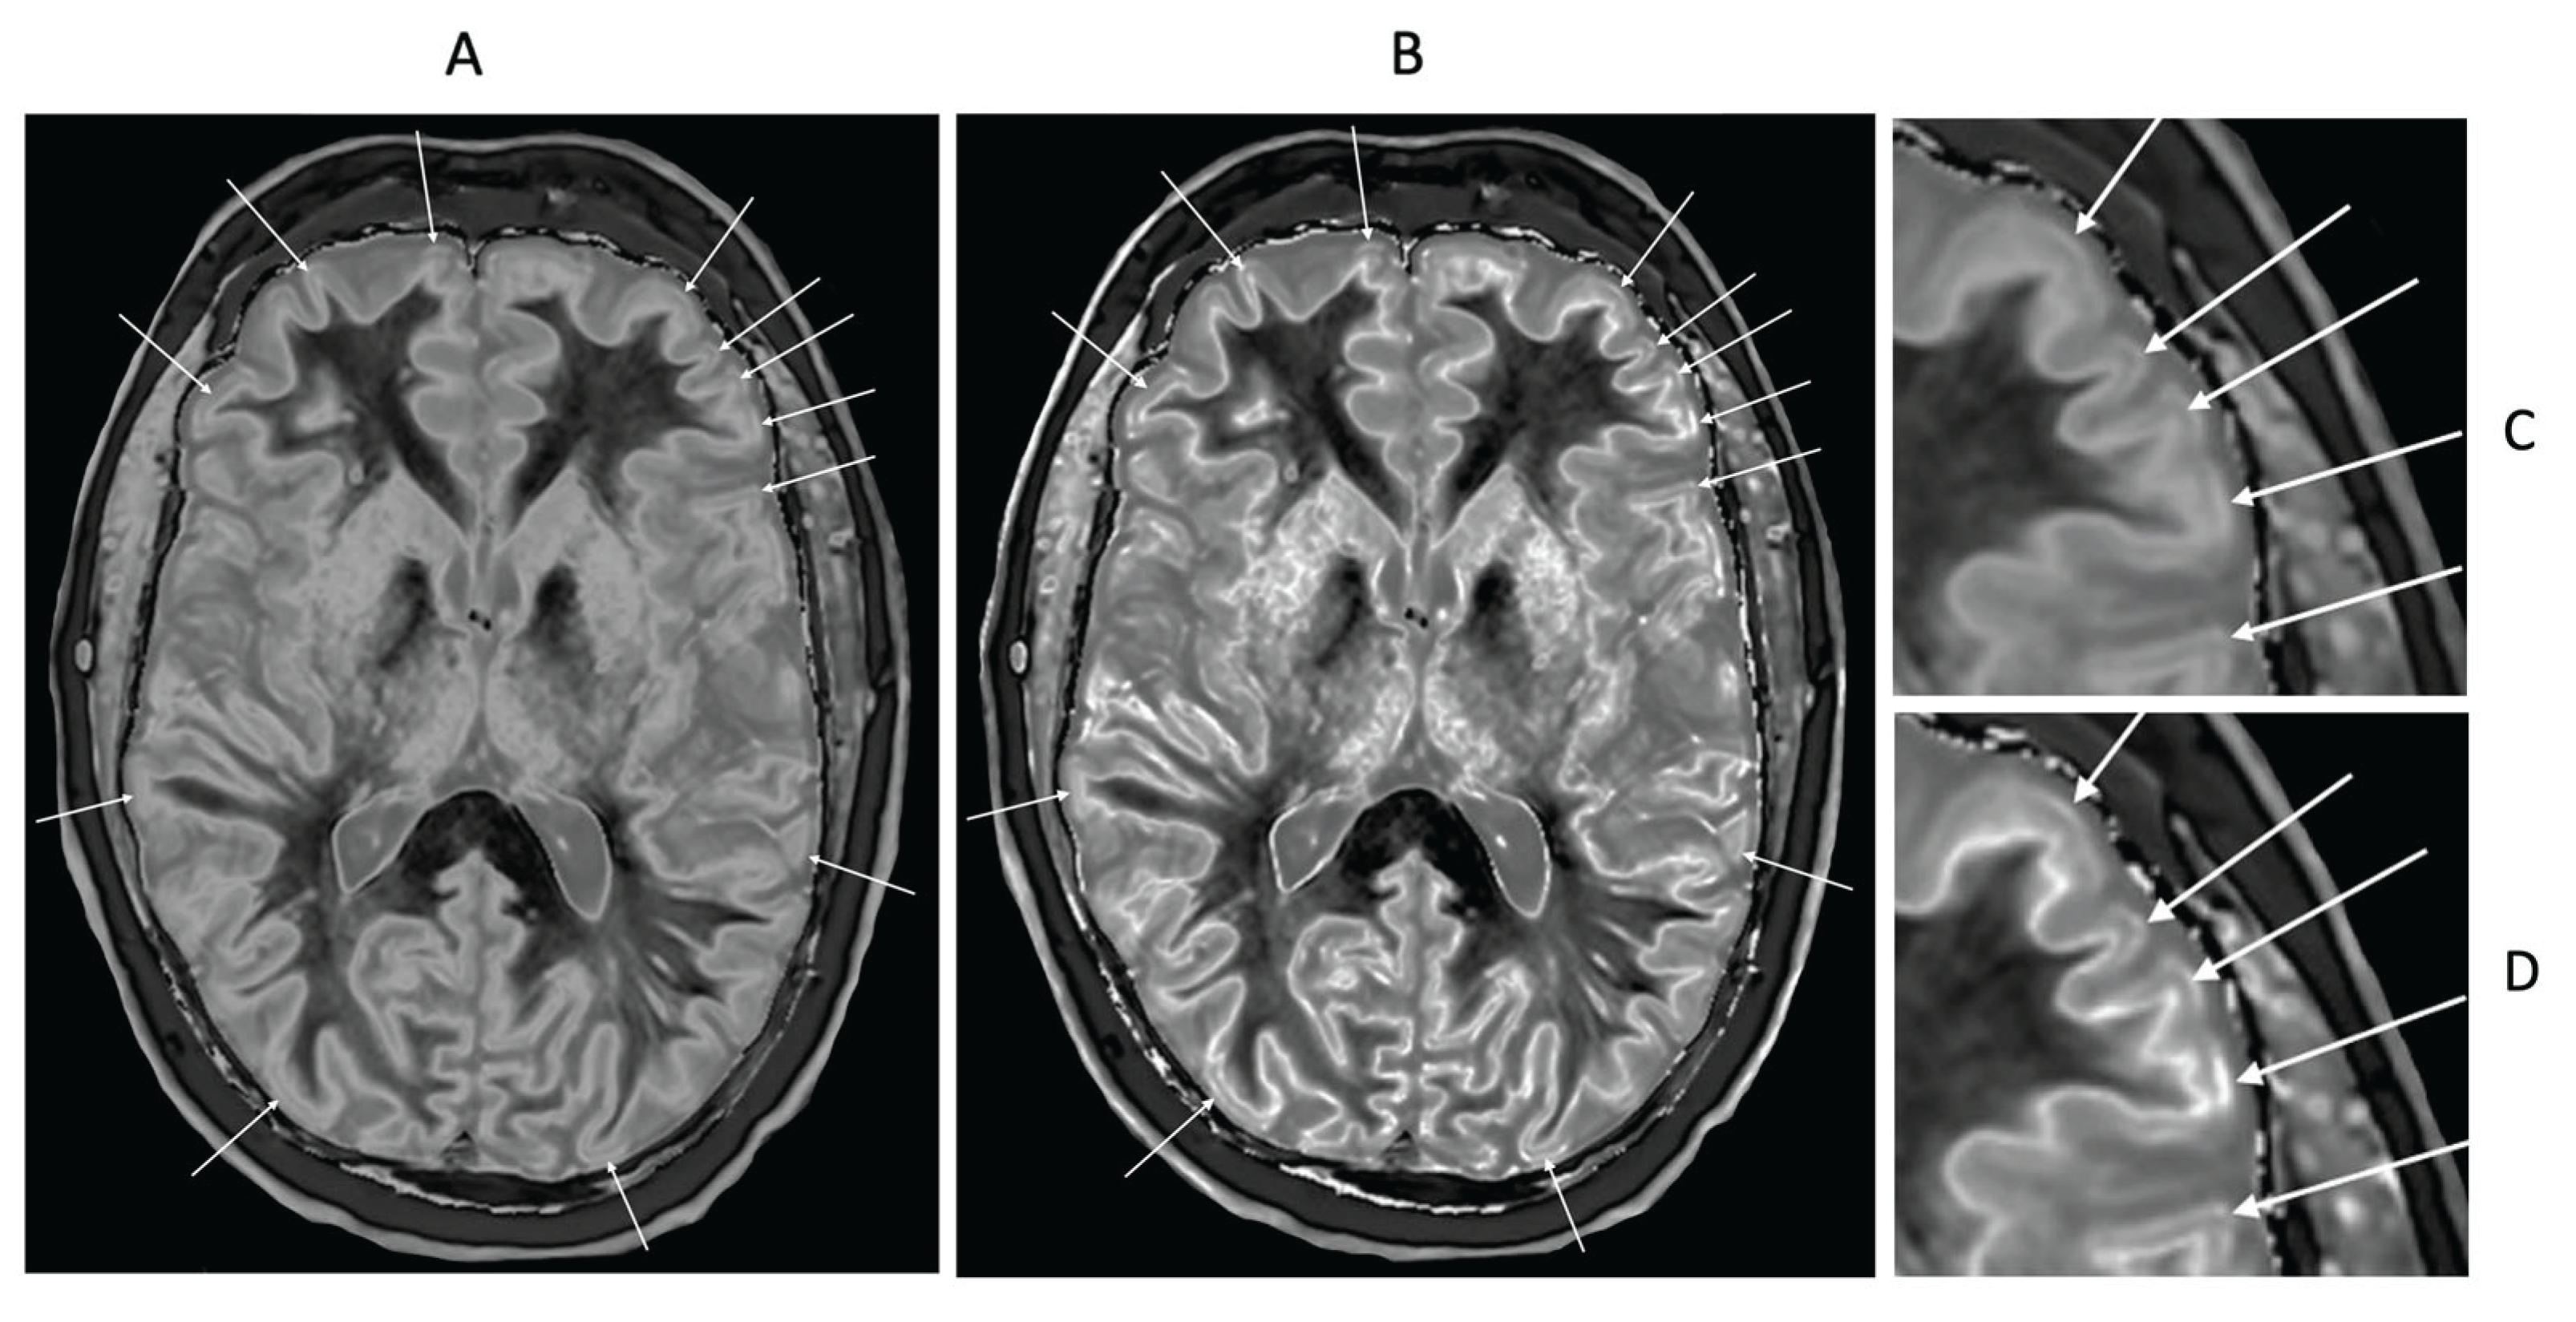

- Multiple Sclerosis (MS)

- Normal Control and MS Patient with dSIR and lSIR Images